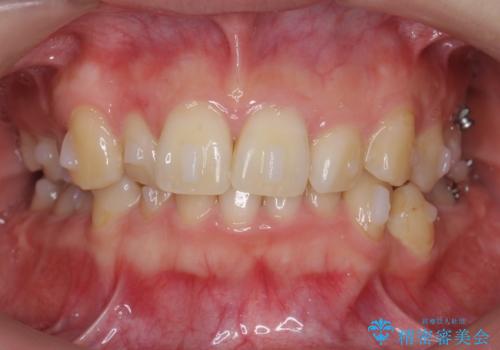

奥歯を後ろに送るために、矯正用ミニスクリューを使用しました。

また、下顎の前歯から奥歯にかけて歯を少し削るIPRを行なっています。

矯正治療開始前におすすめした根管治療の場所がありましたが、患者様の強いご希望により、無視して矯正を開始しました。矯正開始後に、痛みが出て他院で根管治療を行なった影響で、矯正治療を一時中断しました。その影響で矯正治療の期間は長引きましたが、実質一年台で終わったと思います。